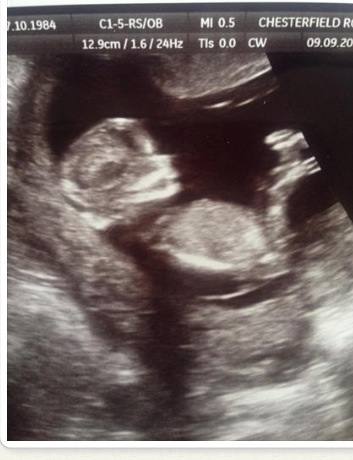

Last pic shows the most visible nub. I'd say def a girl, considering you're beyond 13 weeks.

If you were earlier, I'd have said boy. But given you are beyond 13 weeks, I think we would see more rise if it were a boy. So I tentatively lean girl.

Pink but I agree with above. If you weren't at 13 weeks I would have thought the nub was on the rise.